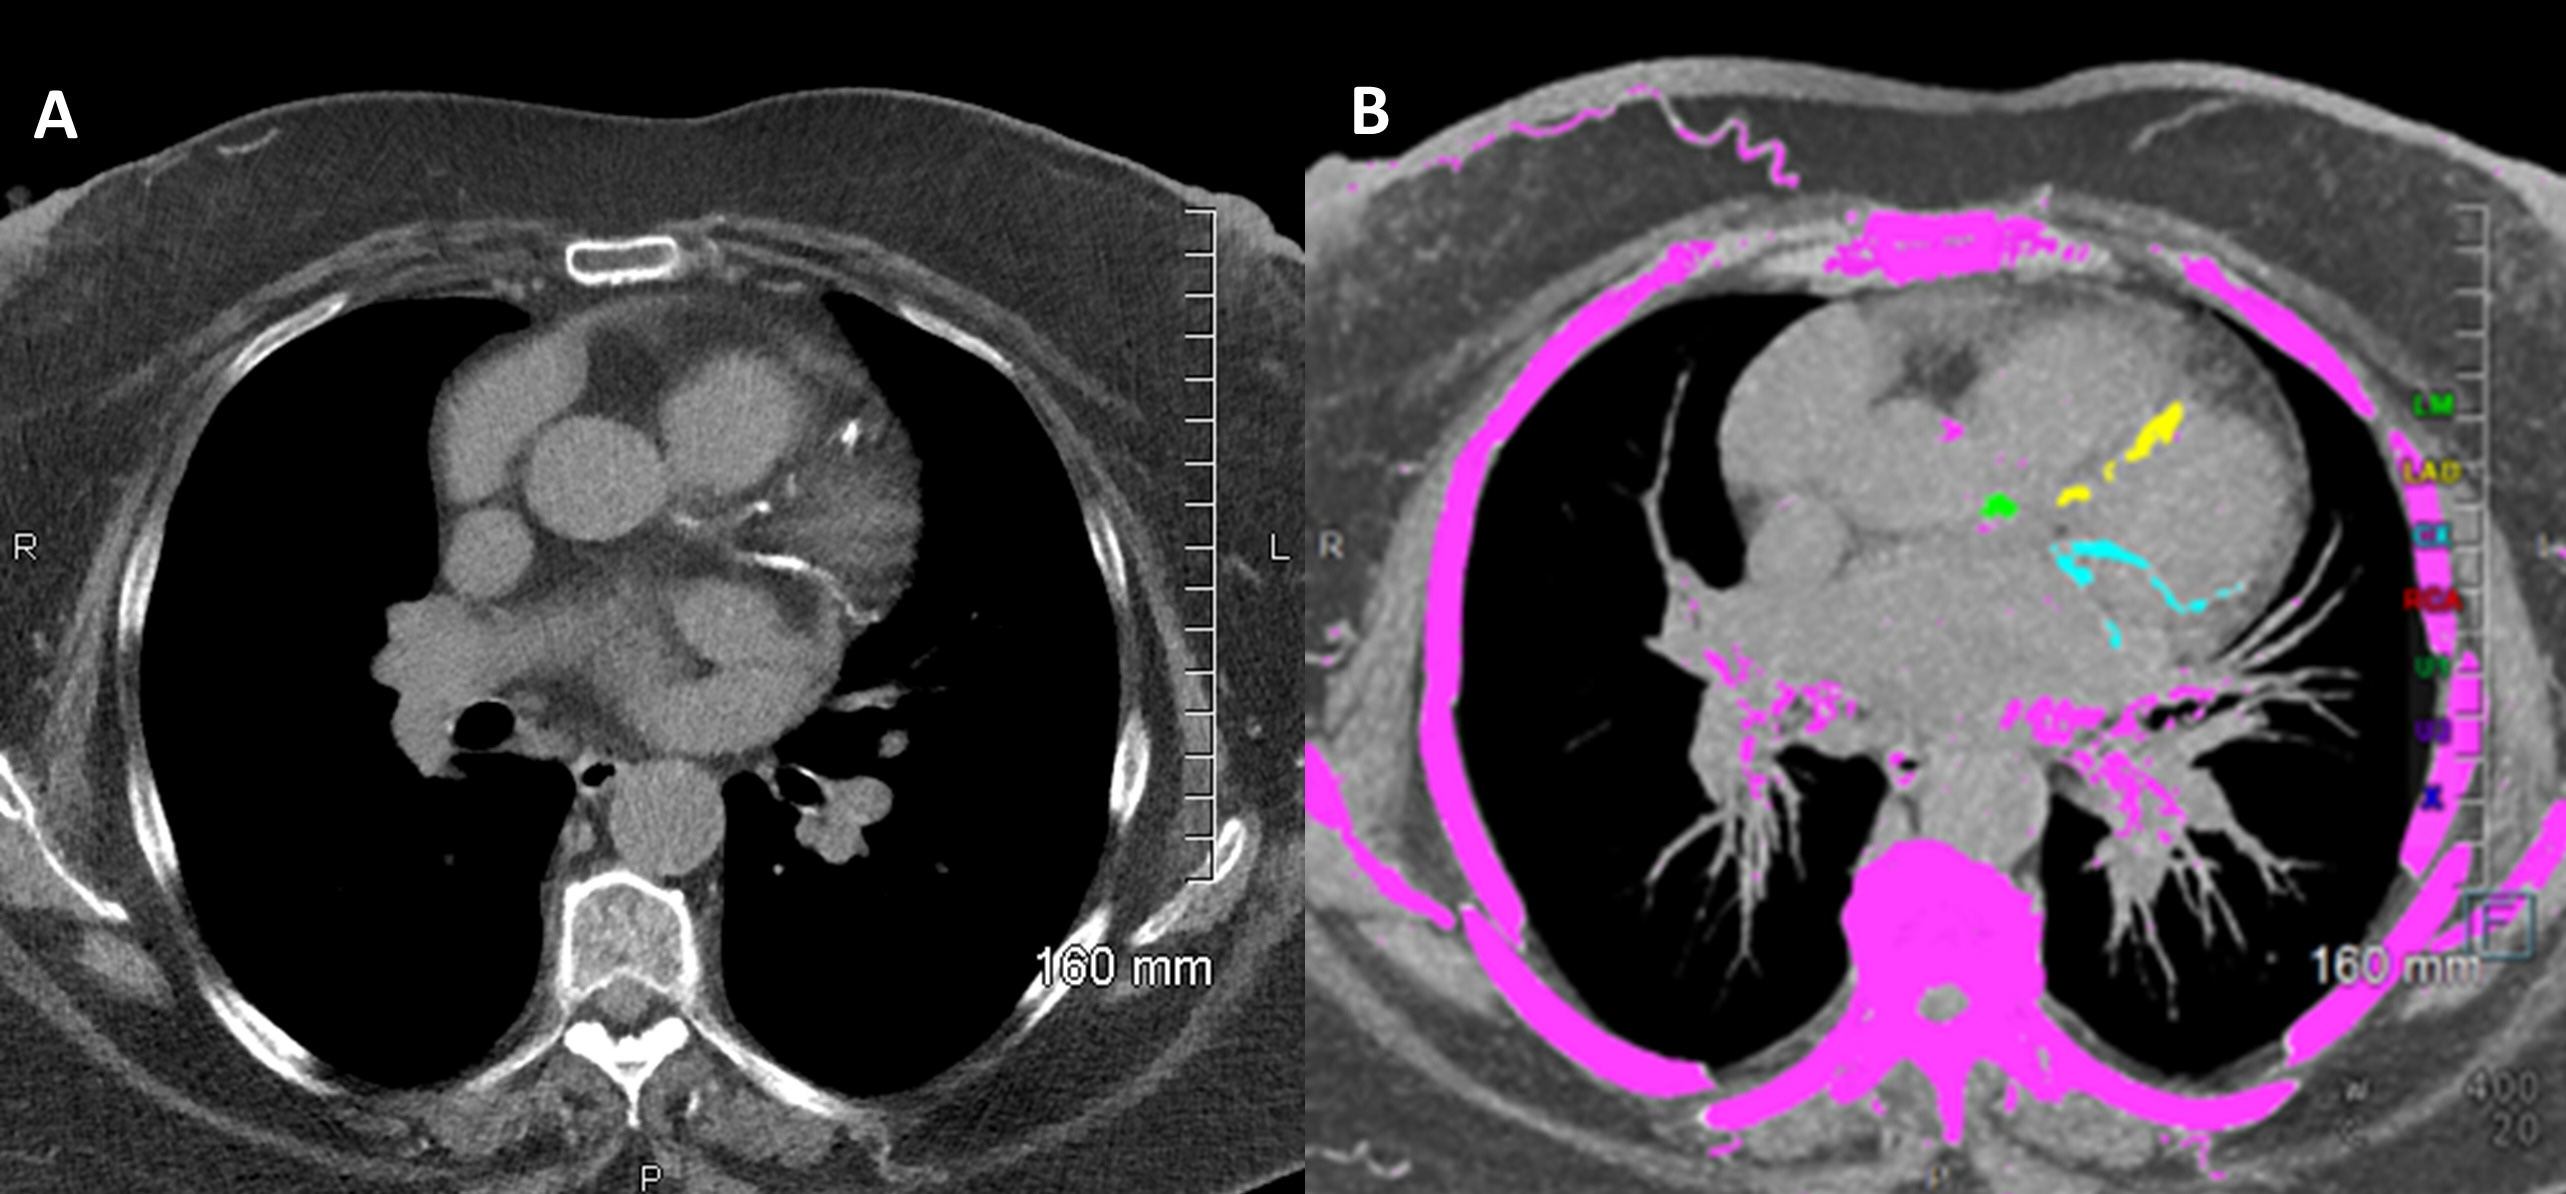

A coronary artery calcium (CAC) scan is a fast, non-invasive test that detects calcium buildup in the arteries of your heart—an early indicator of atherosclerosis and your future risk of heart disease.

Image Analysis: Understanding Your CAC Score

Once your scan is complete, the images are analyzed to calculate your Coronary Artery Calcium (CAC) score—a numerical value that reflects the total amount of calcified plaque in your coronary arteries.